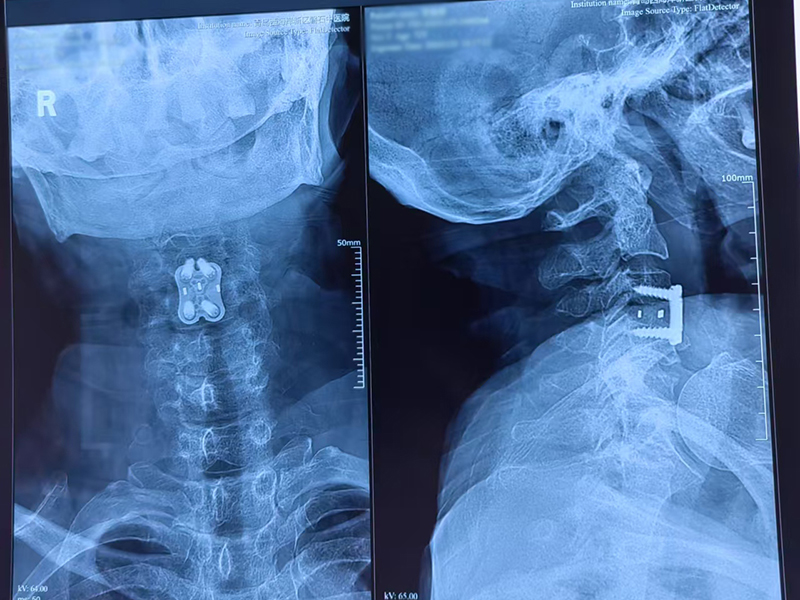

今日我院外科团队举全院之力完成了脊柱外科首例脊髓型颈椎病颈椎前路手术。一例真正意义的四级手术。患者女性,72岁,右下肢麻木无力3个月来本院,有高血压病,冠心病,糖尿病,直肠癌手术史。经过详细问诊查体和影像学检查,确诊脊髓型颈椎病合并脊髓半切损伤。我院郭院长带领进行了术前多学科讨论,相关科室给予全力配合和支持,手术顺利完成,现在恢复良好。病人和家属非常满意。